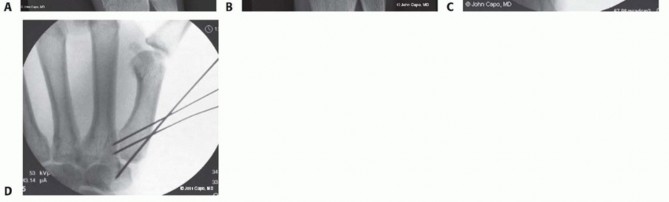

Closed Reduction and Percutaneous Pinning (CRPP)

CRPP is the treatment of choice for classic Bennett fractures where the volar-ulnar fragment is too small to reliably accept a lag screw, yet the joint can be anatomically reduced closed. The reduction maneuver is highly specific, designed to counteract the deforming forces of the APL and Adductor Pollicis. Longitudinal traction is applied to the thumb, followed by palmar abduction and pronation. Direct pressure is then applied to the dorsal-radial aspect of the metacarpal base, effectively pushing the shaft back into the anatomic cradle of the intact volar-ulnar fragment.

Once anatomic reduction is confirmed via multi-planar fluoroscopy, percutaneous fixation is achieved. Typically, two 0.045-inch or 0.062-inch Kirschner wires are utilized. The first wire is driven from the dorsal-radial aspect of the metacarpal shaft directly into the trapezium, effectively neutralizing the proximal pull of the APL. A second wire is often placed transversely from the first metacarpal shaft into the second metacarpal to control rotation and maintain the web space. Pins are cut outside the skin and capped to facilitate easy removal in the clinic.